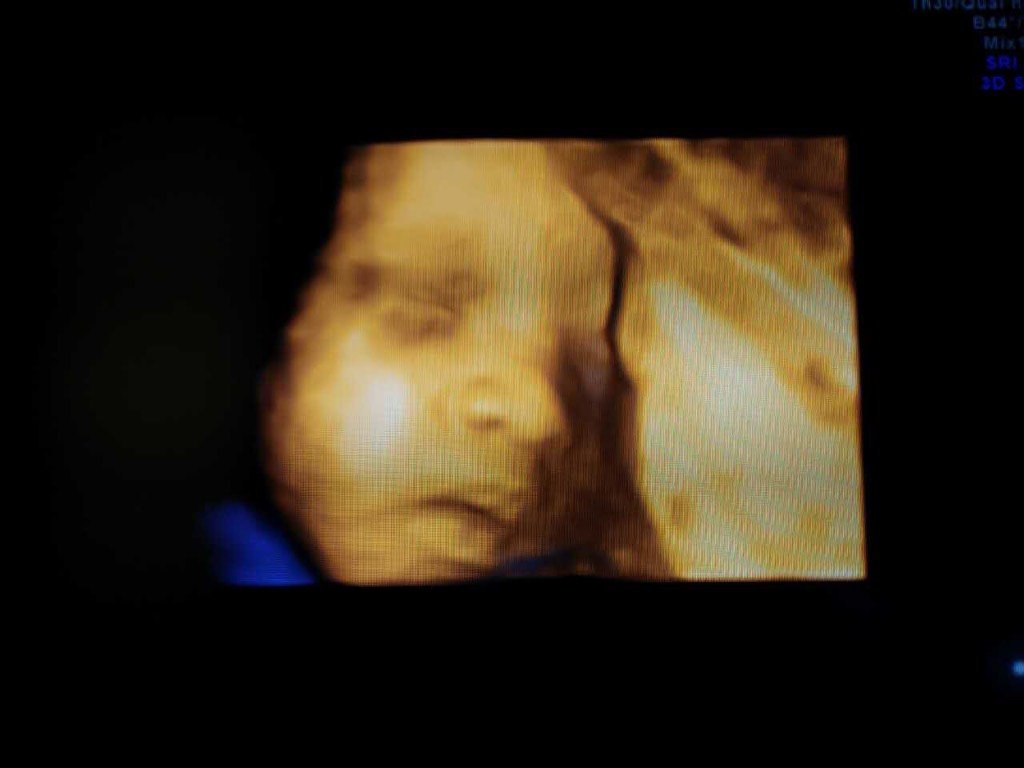

宝妈们,帮看看是男孩女孩

我看也像男孩,我家的是女宝